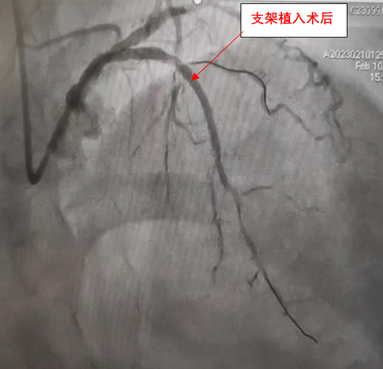

手术在洪浪教授的指导下进行,手术方案采用正向导丝技术、球囊拘禁策略保护第一对角支。经过多种特殊导丝的尝试,最终证实gaia 3导丝在血管真腔,植入2枚支架,手术总时间不到2小时。由于入路采用了左右桡动脉,做完手术立即就可以下床活动。术后患者对医护团队竖起大拇指:“找洪浪教授就是安心,真心为您们高超的医疗技术点赞,感谢您们的辛苦付出!”